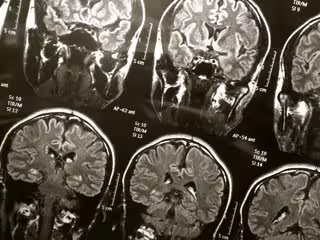

El diagnóstico de Alzheimer por escáneres cerebrales mejora el manejo del pacientes

Cerebro

FLICKR/WYINOUE - Archivo